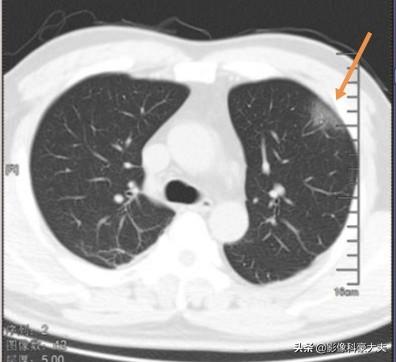

Cette fois, le nouveau coronavirus ressemble à une couronne avec de nombreuses petites protubérances à sa surface, qui peut adhérer à l'épithélium alvéolaire de type II grâce à la protéine échinocandine, pénétrer dans les cellules et les répliquer comme des voleurs qui forcent les serrures, ce qui entraîne la mort des cellules, provoquant une inflammation locale et une ombre de verre pilé sur le scanner :

Dans certains cas, l'organisme est résistant ou sensible au traitement, et les lésions peuvent être rapidement résorbées et s'améliorer, voire dans certains cas ne pas laisser de traces.

Un petit nombre de patients gravement atteints continueront à progresser, avec des lésions de plus en plus grandes et même la formation de poumons blancs. Cette maladie grave est le plus souvent observée chez les personnes âgées, en particulier celles qui souffrent d'hypertension artérielle, de diabète et de broncho-pneumopathie chronique obstructive (BPCO).